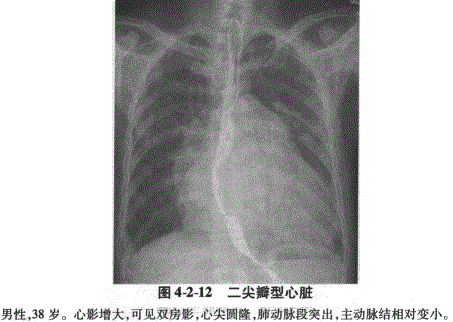

1.二尖瓣型:常见于二尖瓣狭窄。后前位:早期心底部出现圆形或椭圆形密度增高影,逐渐在右心缘出现双心房影;胸主动脉下段向左侧移位,左支气管被向左上方推移,支气管分叉角增大;在肺动脉段与左心室段之间出现增大的左心耳段,称为第三弓(图4-2-12)。侧位:左心房段向后方压迫食管,心后间隙变小(图4-2-13)。